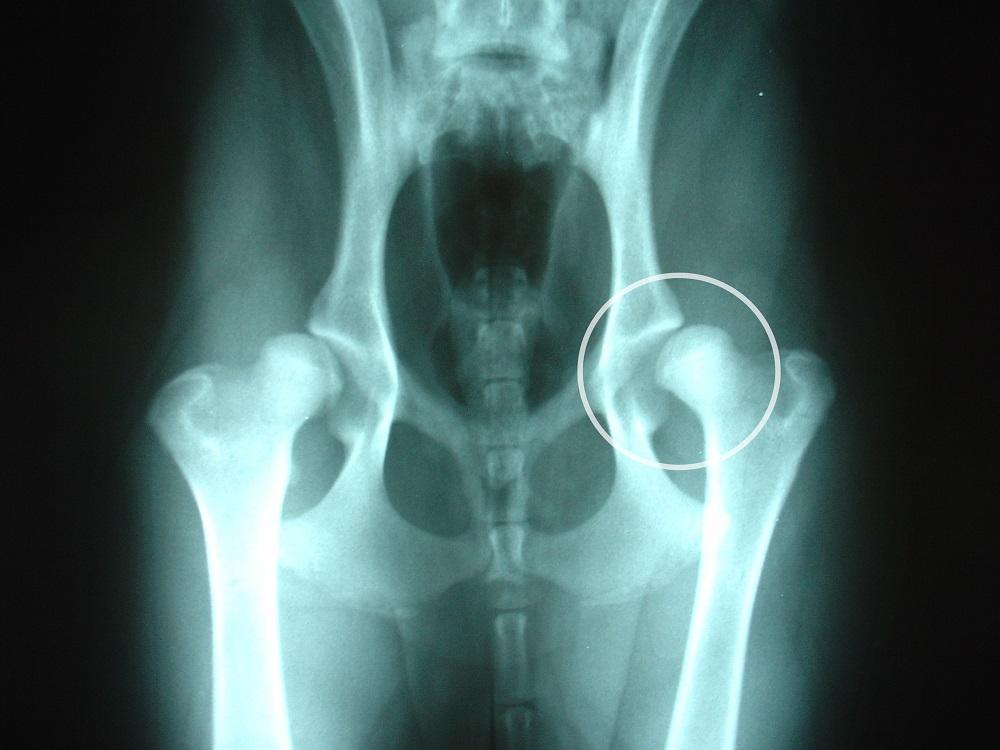

Displasia de cadera

La displasia de cadera puede afectar a cualquier perro pero especialmente a perros de raza grande. Se trata de una patología que impide el adecuado desarrollo de la articulación de la cadera durante el crecimiento, ésta se desplaza hacia los laterales y con el tiempo afecta al movimiento.

A causa de esta malformación el perro tendrá dificultad en realizar sus actividades cotidianas, experimentando dolor y en ocasiones cojera. Se trata de una enfermedad hereditaria por lo tanto es importante que en el criadero te expidan un certificado conforme a que los padres del ejemplar que adoptas no padecen esta patología.

Para evitar que el akita americano desarrolle displasia de cadera es importante que evite los movimientos y ejercicios bruscos hasta alcanzar el año de edad. No obstante, una vez nuestro perro desarrolle esta enfermedad debe seguir ejercitándose para evitar la atrofia muscular